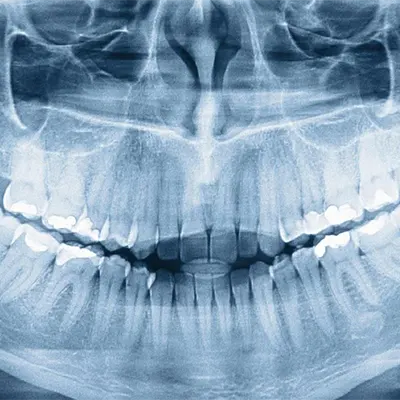

Chowdhury’s Premium Dental offers advanced X-ray services for accurate diagnoses and personalized treatment plans. Our state-of-the-art digital X-ray technology detects hidden issues, enabling us to assess oral health conditions and deliver precise care. Trust our expertise and the latest techniques for comprehensive, efficient dental services tailored to your well-being.